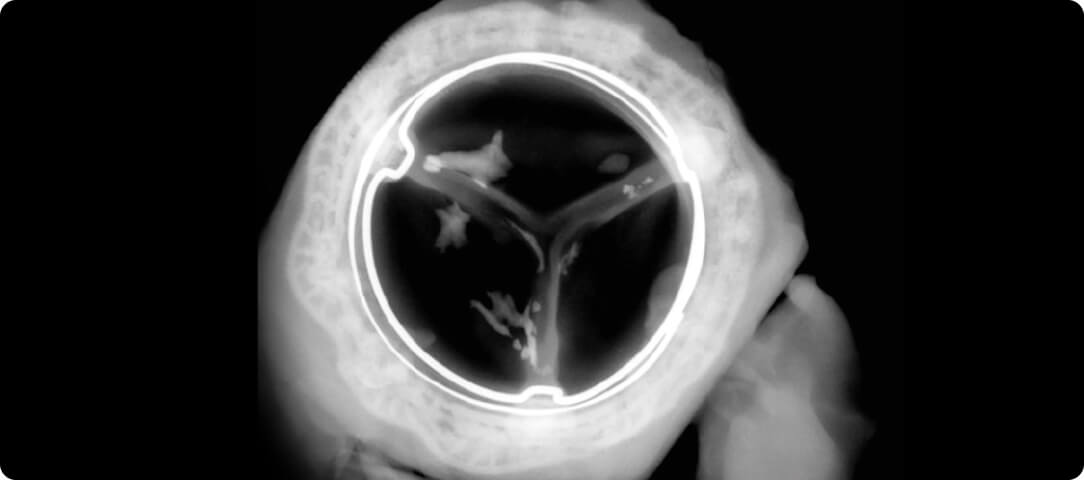

Explanted valves from an animal study1 showing less calcium build-up in the valve with RESILIA tissue compared to the valve with regular tissue.*

*RESILIA tissue has not been studied for long-term results in patients.